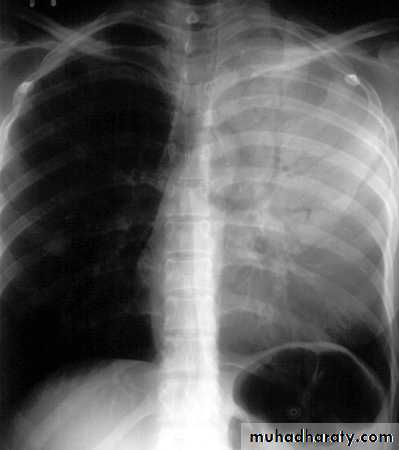

• LOBAR PNEUMONIA

Right lower lobe consolidation - PA. Dense opacification in the right lower zone with effacement of the outline of the right hemidiaphragm.

• Right lower lobe consolidation - Lat.

• The density lies posterior to fthe oblique issure- the position of the lower lobe.